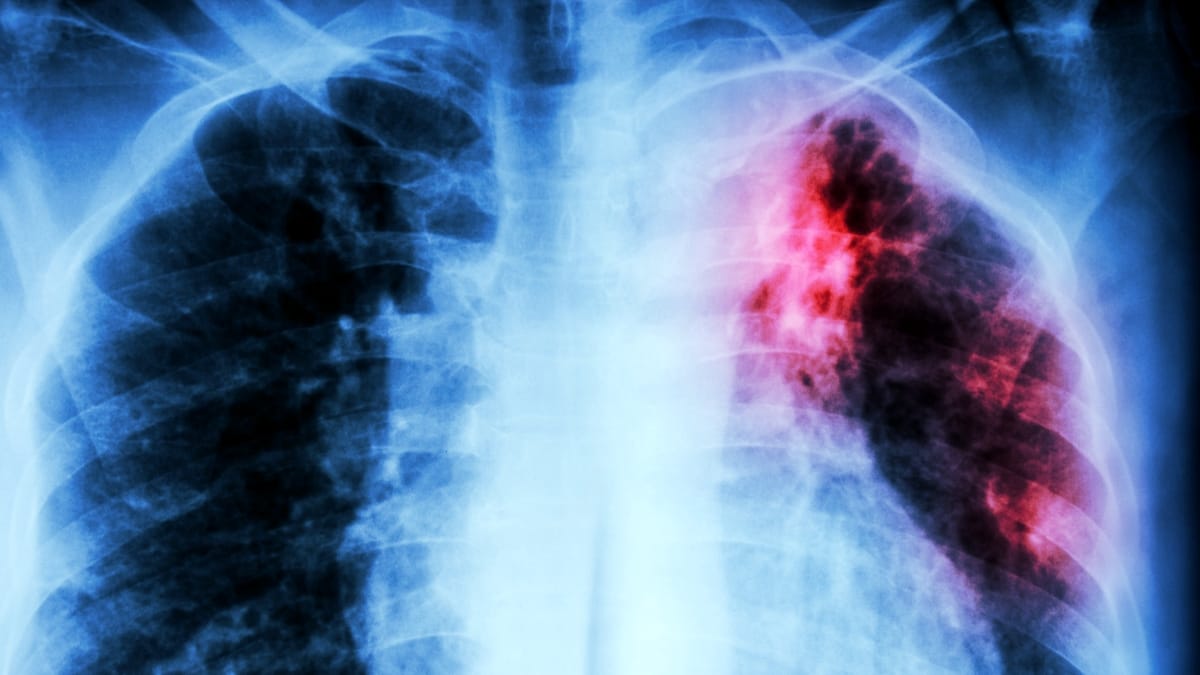

Após décadas de declínio em regiões desenvolvidas, a tuberculose (TB) registra um aumento preocupante, tornando-se cada vez mais resistente aos melhores antibióticos disponíveis. A OMS alerta para esta crise de saúde pública, classificando a TB como a principal causa infecciosa de mortes no mundo, com mais de um milhão de vidas perdidas anualmente. A doença, transmissível por gotículas aéreas (tosse ou respiração), embora curável, enfrenta desafios significativos: tratamentos eficazes não são universalmente acessíveis, e a duração prolongada dos cursos de medicamentos — que podem levar meses para fazer efeito completo — frequentemente contribui para o surgimento de cepas resistentes a antibióticos. Fatores socioeconômicos e a força do sistema imunológico também desempenham um papel crucial nas chances de sobrevivência de um indivíduo. É importante notar que até um quarto da população global pode estar infectada com a bactéria da TB em estado latente, sem necessariamente desenvolver a doença.